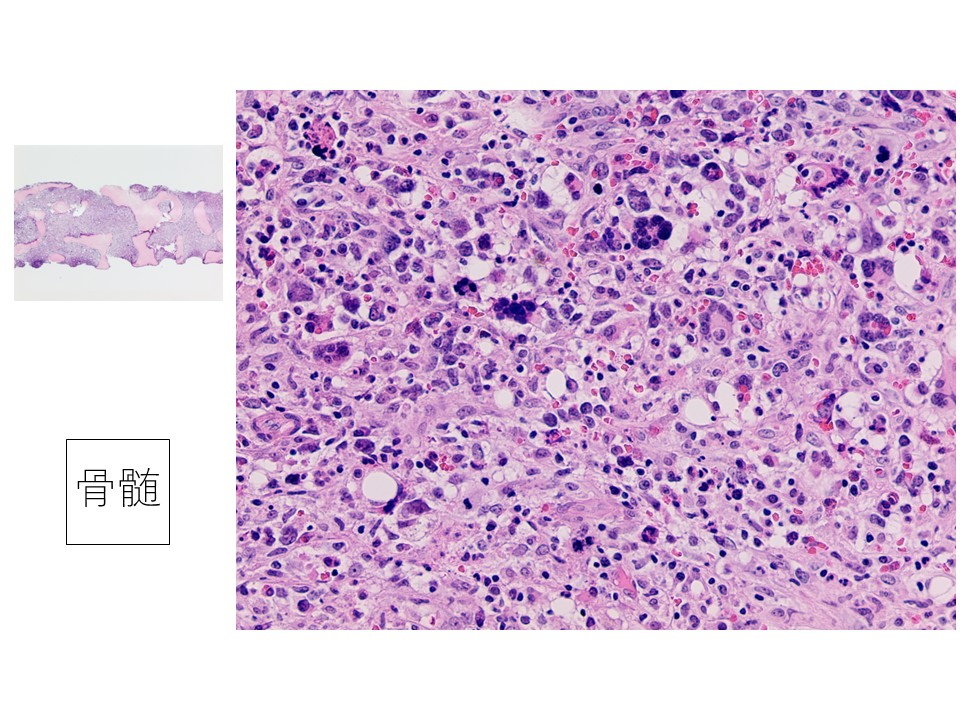

骨髄生検スタンプ:多核の大型異型細胞を散在性に認める。周囲には小型から中型の芽球様の細胞が出現している。大型細胞の細胞質の一部に細胞突起様の存在が疑われる。

骨髄組織:多核で多型性を示す大型細胞が散在し、奇怪な核分裂像を認める。免疫染色の結果FactorⅧとCD61がともに陽性で、急性巨核芽球性白血病と診断。